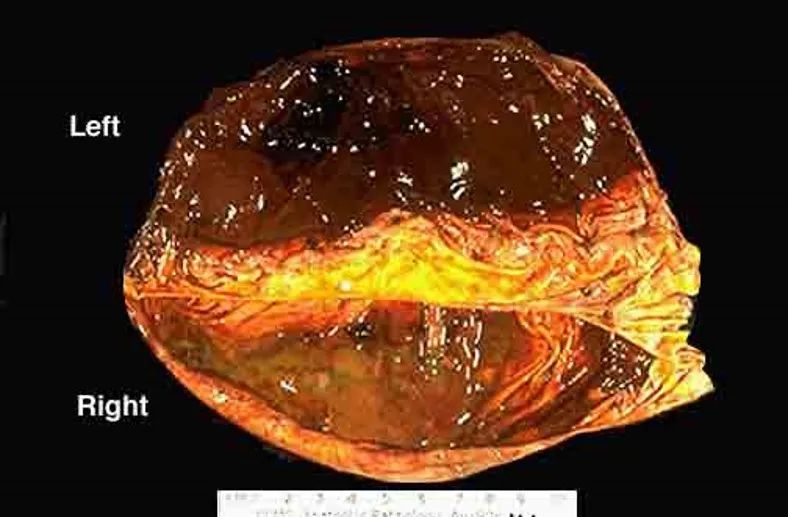

包膜形成。

血肿机化。

增强MRI扫描对发现高龄脑萎缩、血肿分隔多房、包膜形成、血肿机化等有重要作用。

包膜形成和机化型的CSDH治疗

术前诊断明确的病例,直接选择骨瓣开颅;

对诊断不确定的病例,可以先钻孔探查,确定后可再改骨瓣开颅术;

骨窗应足够大,以能全部暴露血肿利于手术切除血肿;

显微镜仔细分离血肿包膜,可减少出血及癫痫的发生;

血肿外膜应完全切除;

在血肿包膜与蛛网膜和硬脑膜分界处可以留少量血肿内膜,用双极电凝或敷贴止血纱严密止血,以防残留血肿外膜继续渗血;

切忌损伤蛛网膜,造成出血和引起脑脊液流出,引起硬膜下积液,造成血肿复发可能。